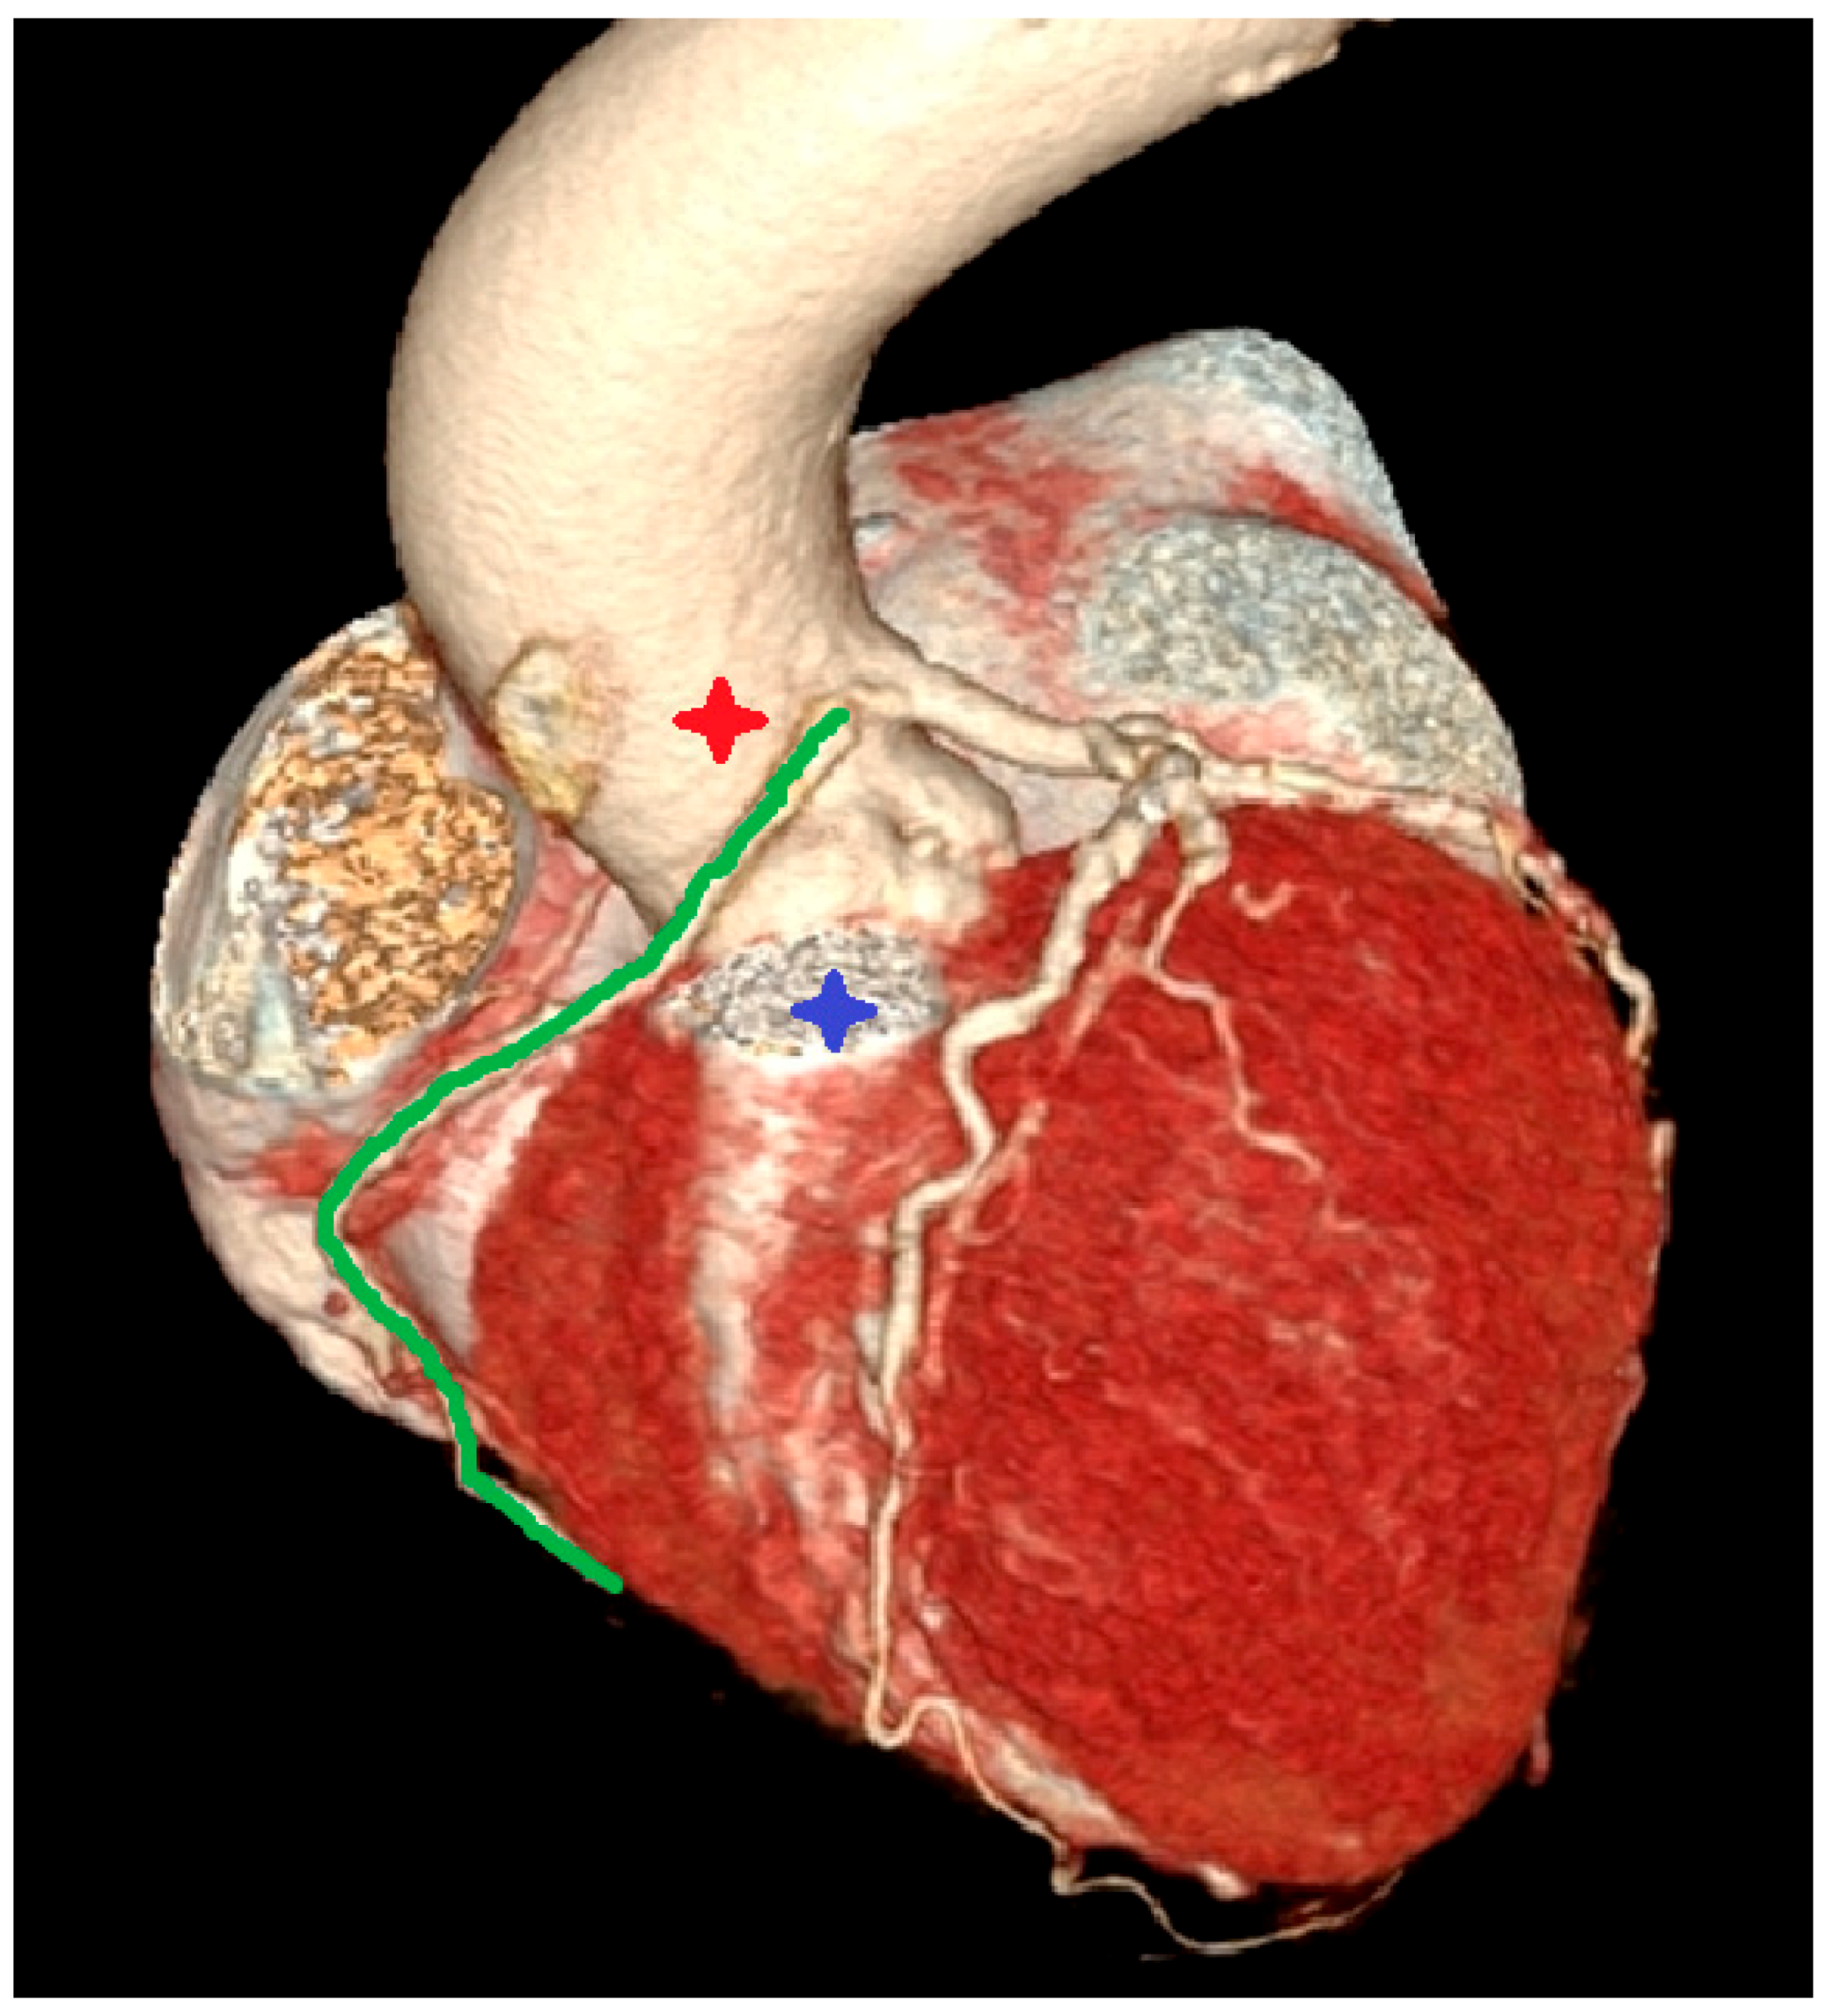

- Incidental vascular finding No. 3: Ectopic Right Coronary Artery Ostium.